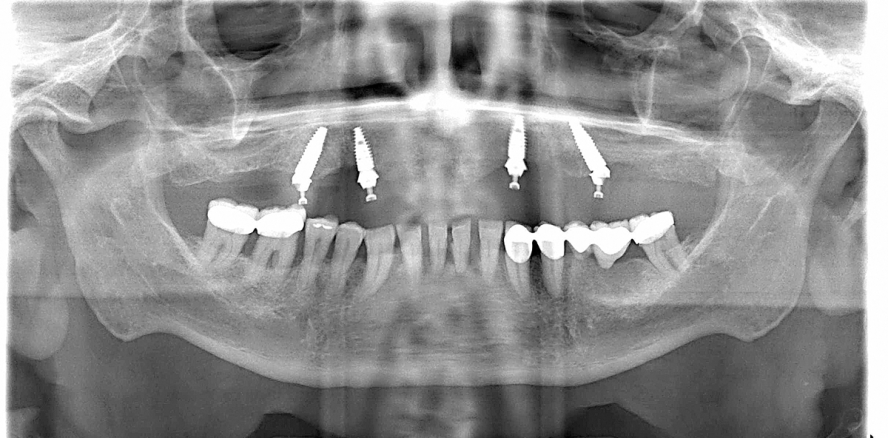

Die klinische und funktionelle Inspektion sowie die röntgenologische Voruntersuchung mittels Orthopantomogramm gaben Auskunft über die vertikalen Knochenverhältnisse und den Restzahnbestand (Abb. 1 und 3). Zur weiteren Therapieplanung nach Extraktion und Ausheilung der Weichgewebe stellte das zahntechnische Meisterlabor eine doublierte und röntgenopake Kopie der zwischenzeitlich unterfütterten Oberkiefer-Interimstotalprothese her, welche mittels Scankörper-Einarbeitung die Guided Surgery Planung (coDiagnostiX) ermöglichte und nach Weiterbearbeitung als Guided Surgery Bohrschablone intraoperativ zur Verfügung stand (Abb. 4 und 5). Als sehr hilfreich erwies sich ebenso, dass in der PC-Planungssoftware die entsprechenden prothetischen Aufbauteile wie beispielsweise verschraubte Sekundärteile inklusive Abwinklungen und Aufbauhöhen direkt auf den Implantaten mitgeplant und passend bestellt werden konnten. Nur noch die Typvarianten der posterioren Sekundärteile (A oder B) wurden intraoperativ festgelegt. So lassen sich die prothetischen Aufbauteile durch die detaillierte Vorausplanung in der DVT-Aufnahme genauestens vorher­sagen. Das zahntechnische Labor kann im Sinne der One-Model Technique auf dem Arbeitsmodell vor der Insertion der Implantate die metallische Gerüststruktur vorbereiten und auf diesem Modell stets weiterarbeiten.

Die chirurgische Intervention im Oberkiefer erfolgte nach dem Guided Surgery Verfahren. Nach Lokalanästhesie wurde beidseitig ein palatinal versetzter, u-förmiger Mukoperiostlappen vom Eckzahn bis in den Bereich des ersten Molaren gebildet, um die palatinale und incisale Auflage der gingival gelagerten OP-Schablone zu gewährleisten (Abb. 6). Zur zusätzlichen Stabilisierung der Schablone wurden nach initialer Aufbereitung Pins eingesetzt (Abb. 7). Nach dem vom Hersteller empfohlenen Protokoll wurden die Vorbereitungen zur Aufnahme von vier Implantaten ­(Roxolid, Bone Level Tapered, Straumann®) abgeschlossen (Abb. 8). Alle Implantate konnten gemäß der Planung inseriert werden und erzielten ausnahmslos eine Primärstabilität von über 35 Ncm (Abb. 9; Regio 16, 26: je Ø 4,1 mm, L 12 mm, Oberflächenspezifikation: SLActive®, Regio 13, 23: je Ø 3,3 mm, L 10 mm, Oberflächenspezifikation: SLActive®). Einer Sofortbelastung stand damit nichts im Weg. Mittels geführter Knochenkonturfräsen wurden bestehende Knochenüberhänge entfernt und die Sekundärteile eingesetzt. Die Auswahlhilfen im posterioren Bereich kamen zum Einsatz, um die Typbestimmung der um 17° gewinkelten Sekundärteile (Regio 16, Typ A, Regio 26, Typ B) zu erleichtern, alle Sekundärteile wurden gemäß der Planung eingesetzt und verschraubt (Abb. 10–13). Die Titan-Übertragungskappen wurden eingesetzt und der Wundverschluss mit resorbierbaren Nähten (MONOFAST, mectron®) durchgeführt (Abb. 14).